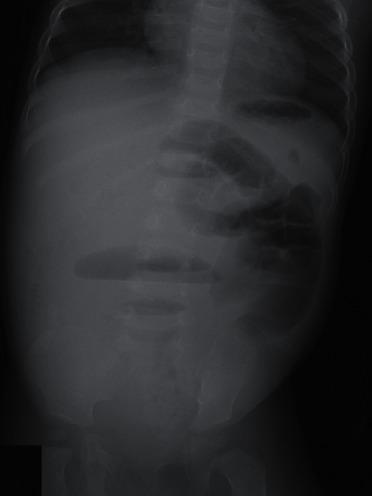

A fecaloma is a mass of accumulated feces with a consistency much harder than that of a fecal impaction. It is most frequently observed in the rectum and sigmoid area, and associated complications include colonic obstruction, ulceration, bleeding, and perforation. A one-year-old, previously healthy boy with no history of chronic constipation was admitted because of vomiting and abdominal distension. An abdominal computed tomography scan showed small and large bowel distension due to multiple obstructive fecalomas in the transverse colon. As the fecalomas could not be resolved by laxatives, enemas, or colonic lavage, endoscopic disimpaction under general anesthesia was attempted. Repeatedly shaving the fecalomas with biopsy forceps finally resulted in gradual fragmentation with subsequent passage. Gastrointestinal food allergy was later suggested as the cause because eosinophilic infiltration was found in a biopsy specimen of the colon wall. Endoscopic disimpaction is an effective treatment approach for addressing fecalomas to avoid more invasive surgical intervention.

粪石是一团积聚的粪便,其硬度远高于粪块嵌塞。它最常出现在直肠和乙状结肠区域,相关并发症包括结肠梗阻、溃疡、出血和穿孔。一名一岁的既往健康男孩,无慢性便秘病史,因呕吐和腹胀入院。腹部计算机断层扫描显示,由于横结肠内多个阻塞性粪石,小肠和大肠均有扩张。由于泻药、灌肠或结肠灌洗均无法清除粪石,因此尝试在全身麻醉下进行内镜下解除粪石嵌塞。用活检钳反复刮除粪石最终使其逐渐破碎并随后排出。后来结肠壁活检标本中发现嗜酸性粒细胞浸润,提示存在胃肠道食物过敏。内镜下解除粪石嵌塞是一种有效的治疗方法,可避免更具侵入性的手术干预。